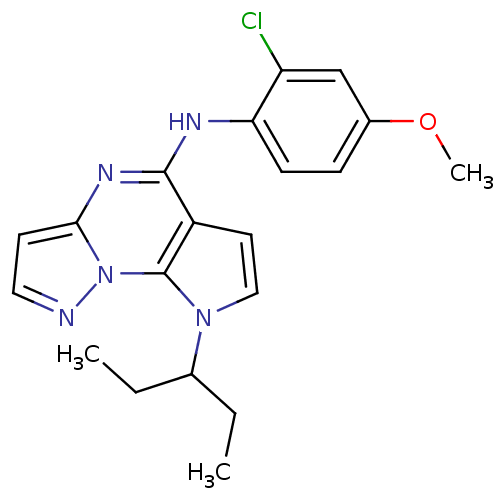

TargetCorticotropin-releasing factor receptor 1(Homo sapiens (Human))

Dupont Pharmaceuticals

Curated by ChEMBL

Dupont Pharmaceuticals

Curated by ChEMBL

Affinity DataEC50: 3.40nMAssay Description:Activity of peptidic agonists on corticotropin releasing factor receptor receptor using agonist-stimulated adenylate cyclase assayMore data for this Ligand-Target Pair